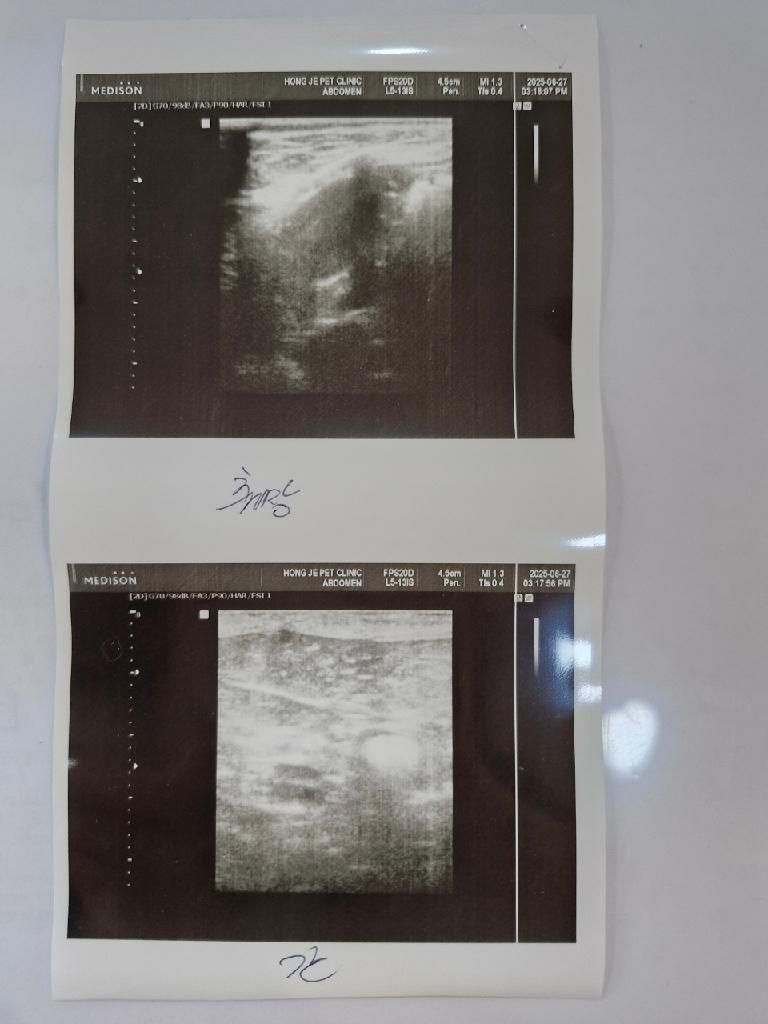

강아지 담낭.. 우루사 먹여도 될까요?

어느병원에선 안된다 어느병원에선 된다 이러니 갈피를 못잡겠습니다

원래는 작년 6-9월경 부터 30퍼센트정도밖에 안차있었는데 노견이면 이정도는 있다 (a병원)

50퍼센트 찼을땐 우루사는 이정도면 과잉처방이다 (b병원)

70퍼센트 찼을때 기억은 잘안나는데 보호자선택사항이다 막힐수도있기에 (c병원)

이런식으로 끌어서 결국엔 이렇게 80퍼센트 이상까지 차게됬습니다 우루사는 단한번도 먹여본적도 없습니다.

현재 d 병원에서 80퍼센트 이상정도 찬거같은데 우루사를 안주실라고했으나 제가 우루사 처방을 d 병원에서 받은 상태이고 초음파도 혈액검사도 모두 여기서 본 그런 상황입니다

강아지 담낭좀 한번 봐주시면 감사하겠습니다 우루사를 먹여도 될 수준인지 봐주세요